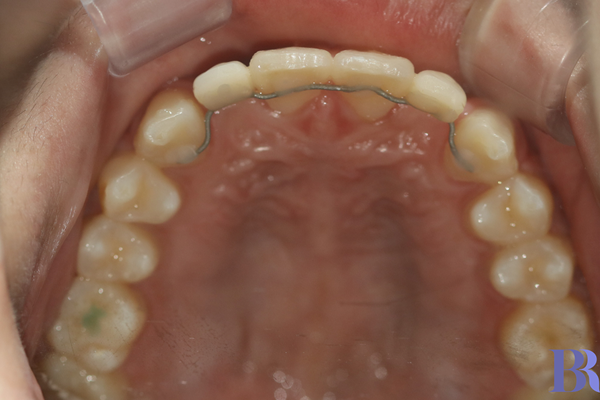

교정 전 윗니 모습

교정 전 윗니 모습입니다

두번째 앞니가 선척적으로

결손된 상태네요.

시간이 갈수록 저 공간은 줄어 들어

반대교합이 심해지겠습니다.